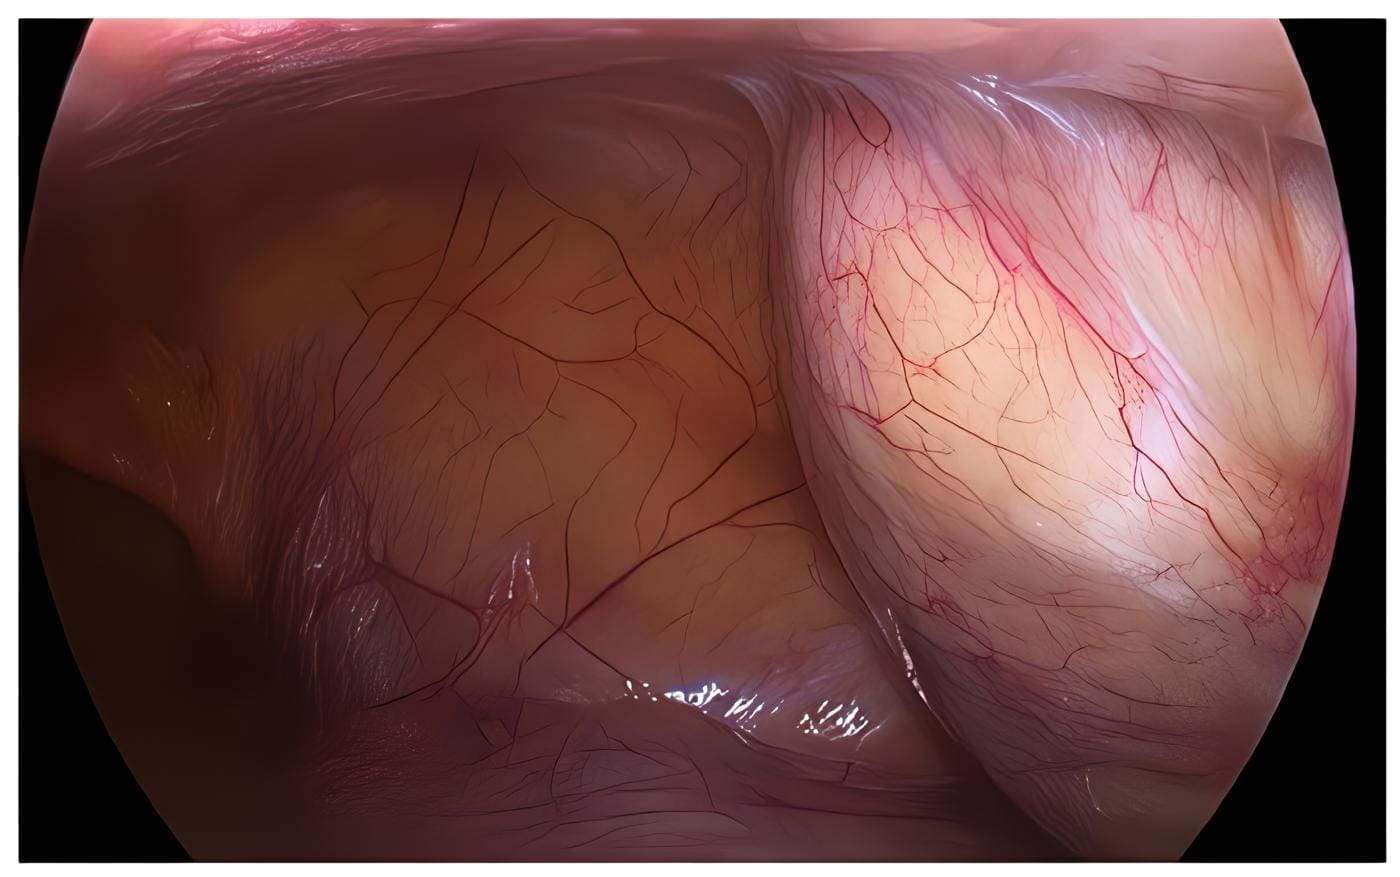

Se llevó a intervención quirúrgica con abordaje laparoscópico, se visualizó tumoración a tensión (figura 3), con contenido gelatinoso y apariencia mucoide, espeso de color amarillo, de las dimensiones referenciadas en las imágenes diagnósticas, ubicada en la pared abdominal de fosa ilíaca y flanco derechos, entre el músculo transverso y el peritoneo parietal anterior.

Figura 3. Abordaje laparoscópico donde se observa la tumoración quística a tensión, con contenido gelatinoso de apariencia mucoide espeso, amarillento, ubicada en pared abdominal de flanco y fosa ilíaca derechos, entre el músculo transverso y el peritoneo parietal anterior. Fuente: fotografía tomada en cirugía por los autores.